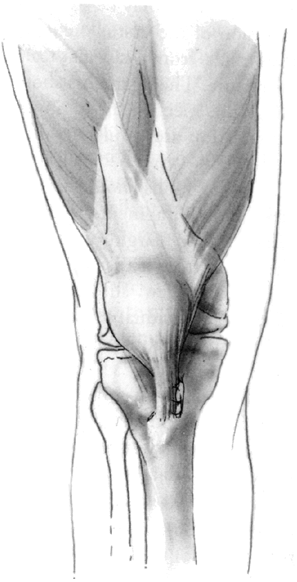

Figure 32.4

The Galeazzi procedure transfers the semitendinosus to the inferior pole of the patella. From there, it courses through a drill hole placed obliquely through the patella, exiting the superior lateral aspect. The tendon is then sutured to the soft tissues. This provides a medial tether and effectively alters the net vector of the patellar tendon toward the medial side. Typically, the vastus medialis is advanced approximately one-third the width of the patella. |